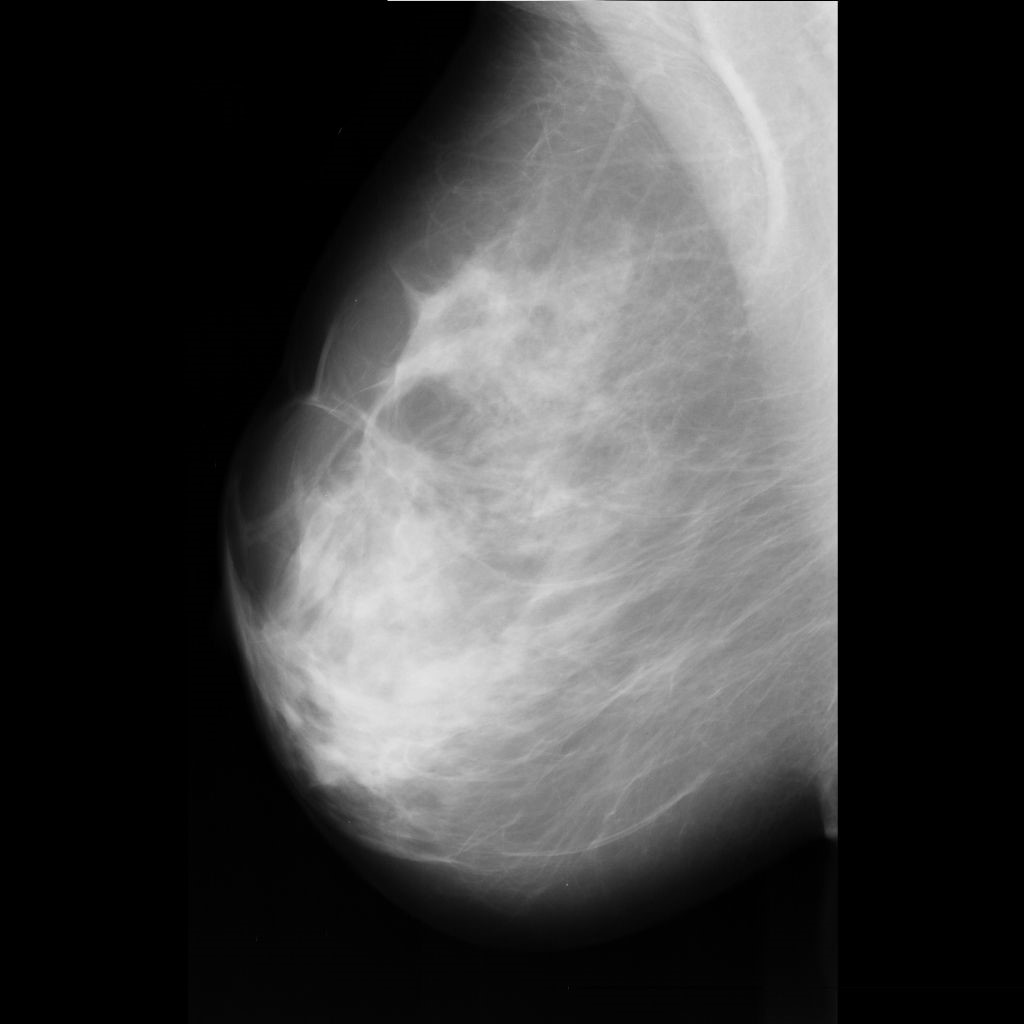

benign